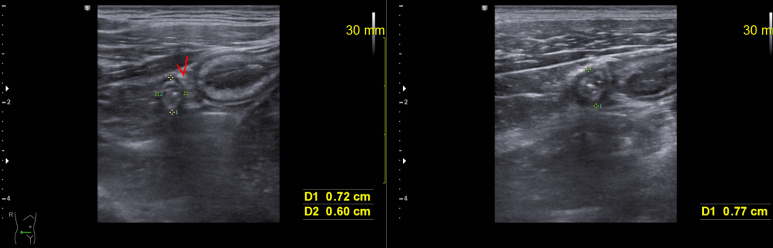

수동 혈압 측정시 불규칙한 맥박이 의심되어 확.. : 네이버블로그 상기 환자 2월에 심초음파 이 당시도 심전도에서 심방세동 상태 다른 소견은 없으나 좌심방의 AP diameter는 3.93 cm, volumn은 54.3 ml/m2 으로 부피...